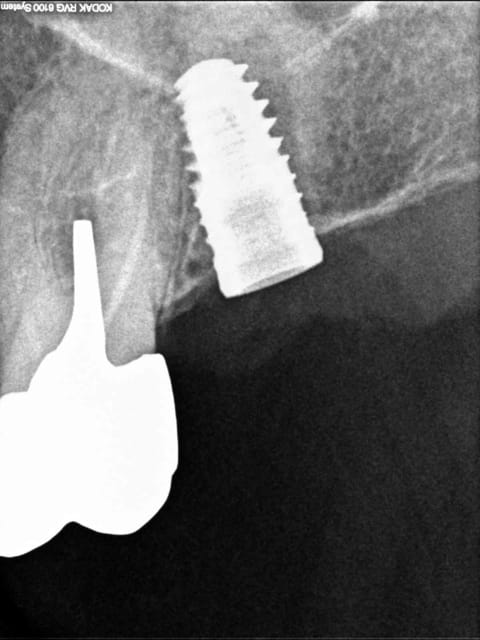

J'ai complètement foiré la pose d'un implant (46)en l'angulant d'une fort mauvaise façon directement au contact de la racine de la dent de devant (45)enfin c'est ce que me montre la radio.....j essaierai de la poster plus tard.

sensibilité de la 45 pas sûr que ça arrive ! je n'ai pas vu la radio mais la dent peut très bien tolérer un implant proche.

Justement par rapport à ton cas la question qui me semble essentielle est : Pourras-tu réaliser la prothèse correctement si ton implant est si mésialé ???

Si c'est pas le cas autant enlever l'implant à 2-3 semaines quand la stabilité primaire est faible en expliquant la chose au patient.

Tiens là aussi contact avec la racine de 26.

Rattrapage aprés retrait et réinsertion de l'implant.

Il ne faut pas non plus oublier qu'une radio n'est qu'une image en 2D, ce qui peut donner l'illusion qu'un implant est au contact de la dent voisine, alors qu'il n'en est rien. D'autant plus que la racine d'une dent naturelle est très proche de la table externe, alors l'axe d'un implant sera plutot centré dans la masse osseuse de la crête.